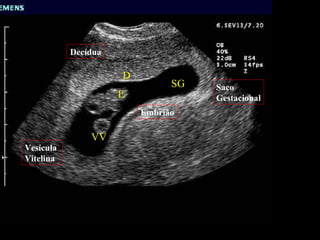

D SG E VV Saco  Gestacional Decídua Embrião Vesícula  Vitelina

D SG EVV Saco Gestacional Decídua Embrião Vesícula Vitelina

Embriologia Fecundação (0 d)    Blastocisto (7 d) Nidificação completa (10 d); o ovo penetra completamente na mucosa endometrial modificada por uma reação decidual as custas da progesterona.

Embriologia Fecundação (0d)  Blastocisto (7 d) Nidificação completa (10 d); o ovo penetra completamente na mucosa endometrial modificada por uma reação decidual as custas da progesterona.